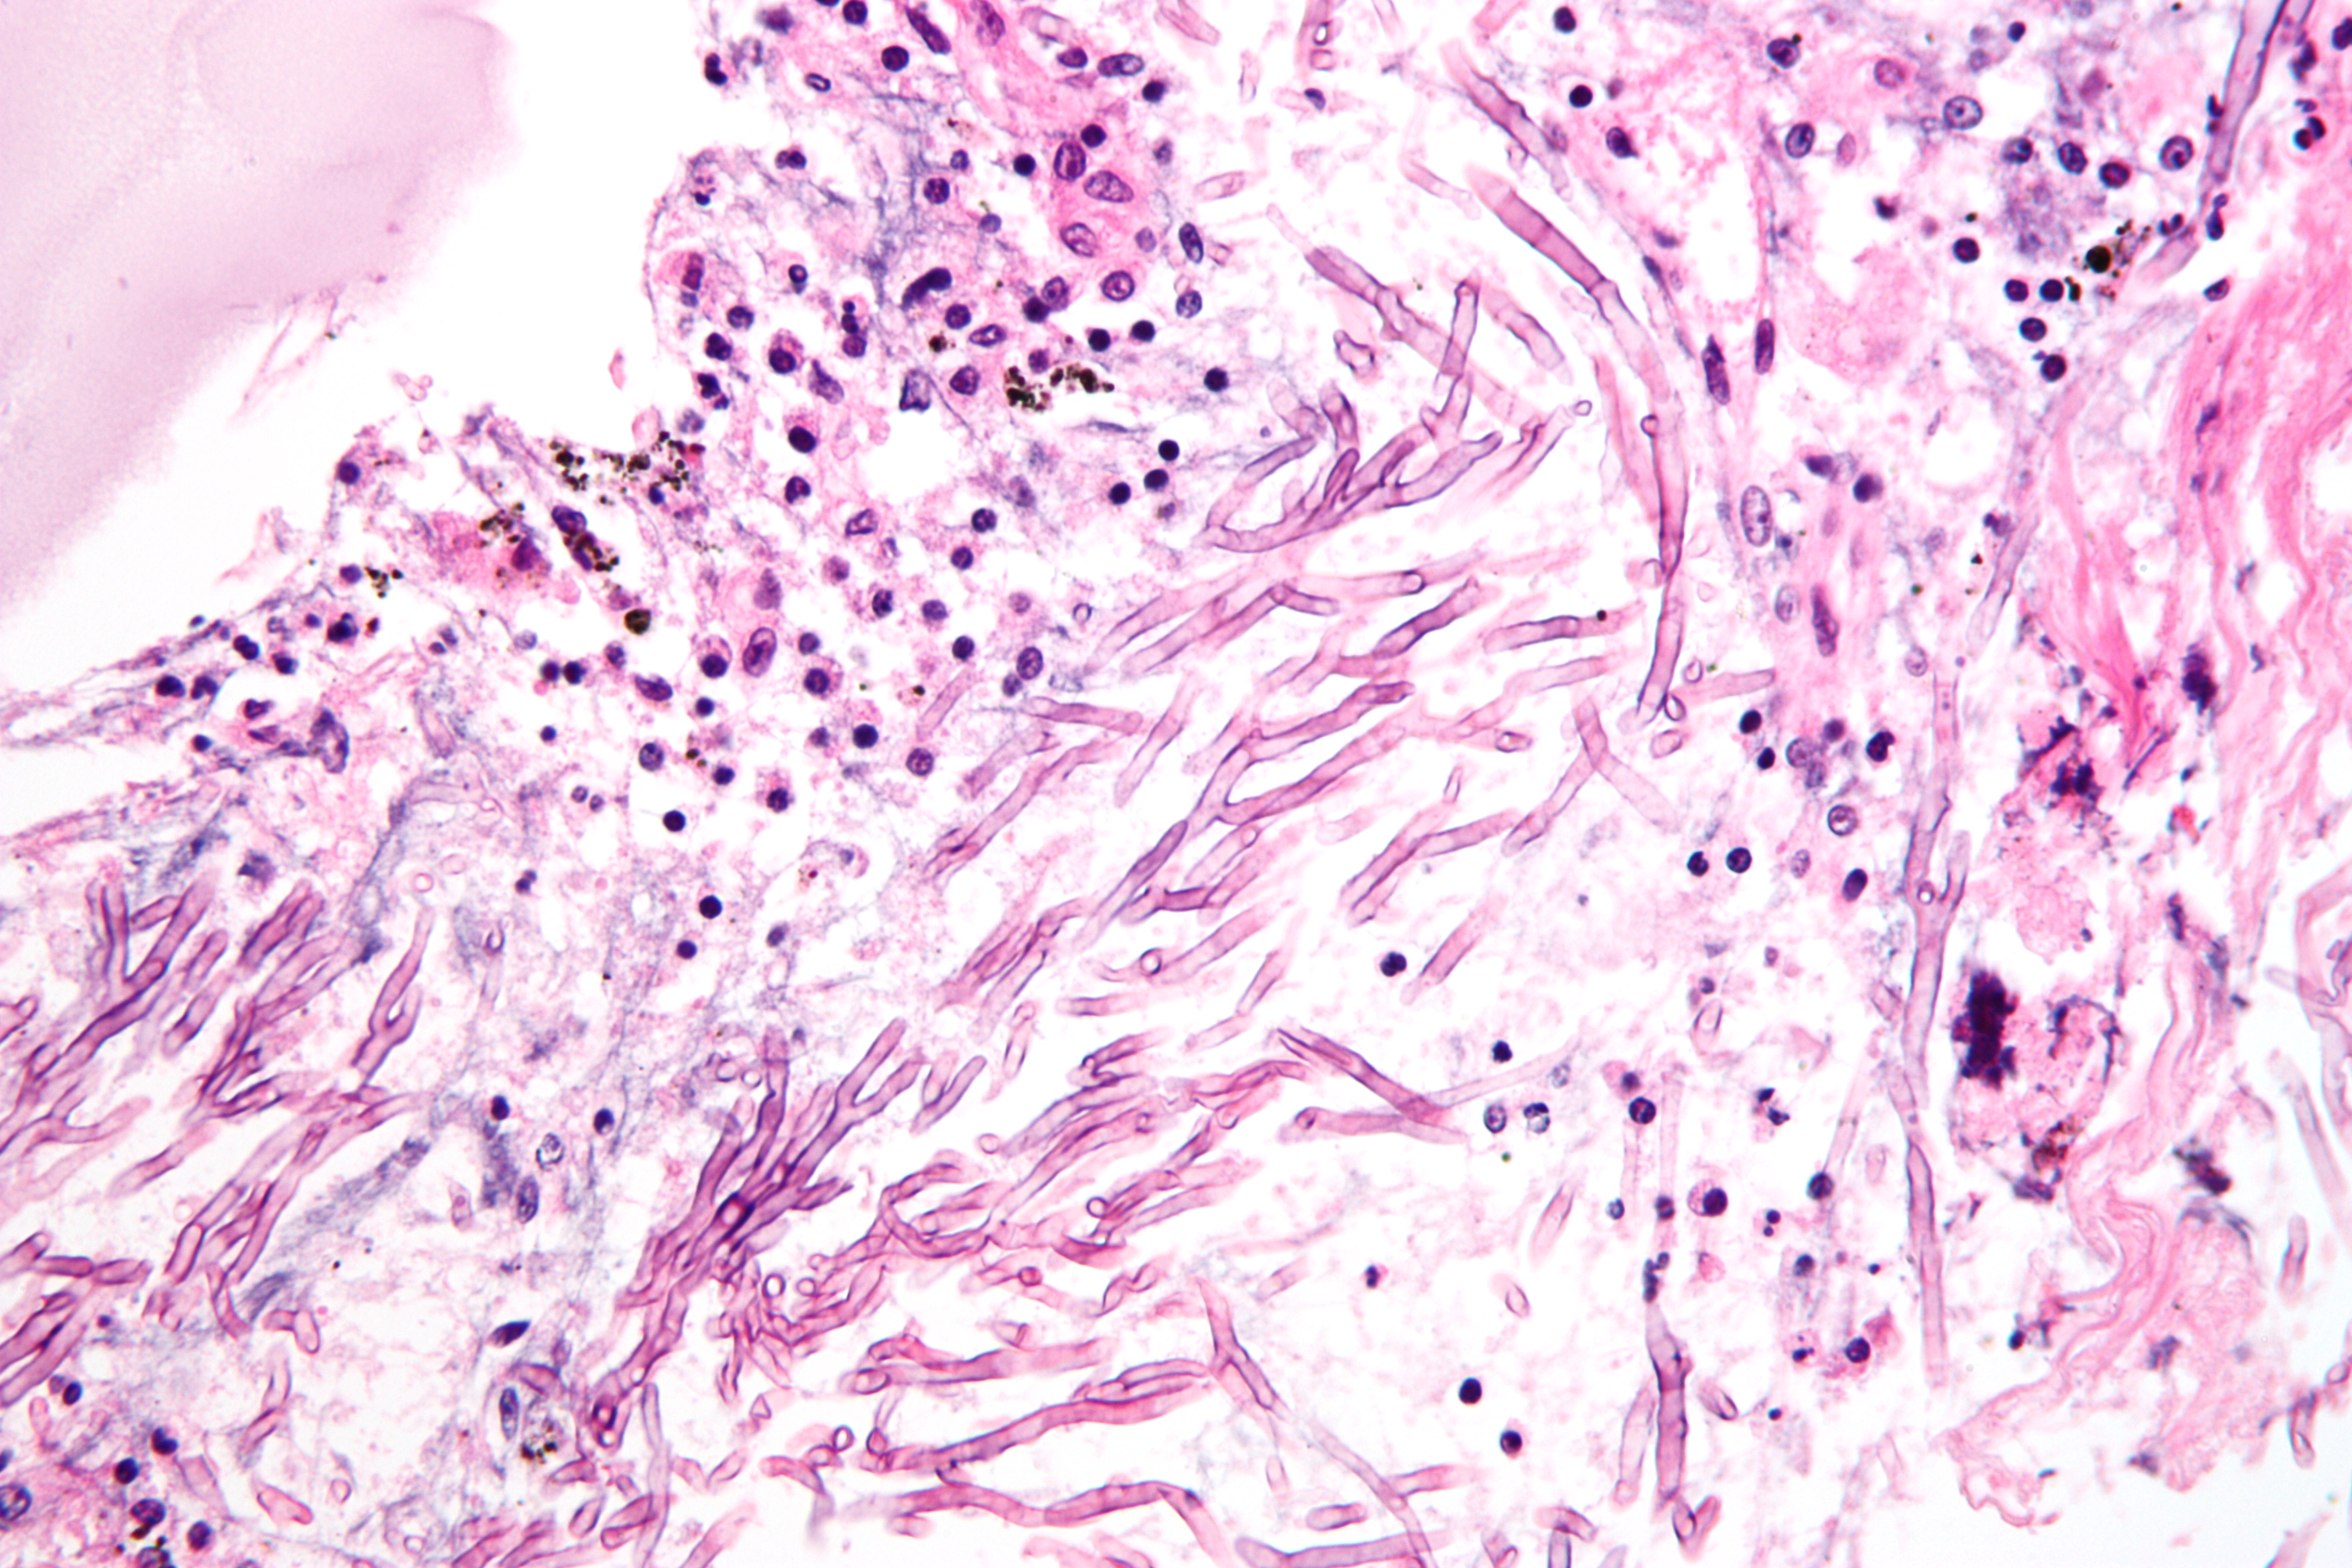

4 key things to know about lung infections caused by fungi discount, Frontiers Pathogenic Fungal Infection in the Lung discount, Fungal Pneumonia Overview Risk Factors Epidemiology of Fungal discount, Pulmonary aspergilloma Information Mount Sinai New York discount, 3 common types of lung fungus Vinmec discount, Fungal Lung Disease Makes World s Deadliest Bacteria Even Worse discount, Fungal infections of the lung in children Pediatric Radiology discount, World s first clinical guidelines for chronic fungal lung infections discount, Pulmonary fungal infection Imaging findings in immunocompetent discount, Frontiers Recent Advances in Fungal Infections From Lung discount, Fungal Pneumonia Overview Risk Factors Epidemiology of Fungal discount, Pulmonary fungal infection Imaging findings in immunocompetent discount, Is it TB or a fungal lung infection New life saving guidelines discount, Fungal pneumonia causes symptoms diagnosis treatment discount, COVID 19 associated pulmonary aspergillosis caused by aspergillus discount, Fungi are present in your lungs Faculty of Medicine UiB discount, Aspergillus Pneumonia Appears to Be Most Common Fungal Infection discount, CT image of lung with pulmonary Candida infection. There are many discount, A Schizophyllum commune fungus ball in a lung cancer cavity a discount, Fatal Fungal Lung infection affects TB recovered patients due to discount, Respiratory Mycoses Microbiology discount, Pulmonary fungal infection Imaging findings in immunocompetent discount, What is Aspergillosis Fungal Infections Symptoms Video discount, Blastomycosis Wikipedia discount, How nanoparticle drug inhalation helps fungal lung infections discount, Aspergillosis Types of Fungal Diseases Fungal Diseases CDC discount, Fungal pneumonia Wikipedia discount, Frontiers Candida Colonization in the Respiratory Tract What Is discount, How to fight fungal infection the path of yeast resistance discount, Pulmonary aspergilloma Information Mount Sinai New York discount, Fungal Infection Not Just Toenails Blueberry Therapeutics discount, Lung disease fungus grows here discount, Frontiers Case Report Invasive Fungal Infection and Daratumumab discount, A case report of fungal infection associated acute fibrinous and discount, Mice found able to ward off fungal lung infections by causing discount.

4 key things to know about lung infections caused by fungi discount, Frontiers Pathogenic Fungal Infection in the Lung discount, Fungal Pneumonia Overview Risk Factors Epidemiology of Fungal discount, Pulmonary aspergilloma Information Mount Sinai New York discount, 3 common types of lung fungus Vinmec discount, Fungal Lung Disease Makes World s Deadliest Bacteria Even Worse discount, Fungal infections of the lung in children Pediatric Radiology discount, World s first clinical guidelines for chronic fungal lung infections discount, Pulmonary fungal infection Imaging findings in immunocompetent discount, Frontiers Recent Advances in Fungal Infections From Lung discount, Fungal Pneumonia Overview Risk Factors Epidemiology of Fungal discount, Pulmonary fungal infection Imaging findings in immunocompetent discount, Is it TB or a fungal lung infection New life saving guidelines discount, Fungal pneumonia causes symptoms diagnosis treatment discount, COVID 19 associated pulmonary aspergillosis caused by aspergillus discount, Fungi are present in your lungs Faculty of Medicine UiB discount, Aspergillus Pneumonia Appears to Be Most Common Fungal Infection discount, CT image of lung with pulmonary Candida infection. There are many discount, A Schizophyllum commune fungus ball in a lung cancer cavity a discount, Fatal Fungal Lung infection affects TB recovered patients due to discount, Respiratory Mycoses Microbiology discount, Pulmonary fungal infection Imaging findings in immunocompetent discount, What is Aspergillosis Fungal Infections Symptoms Video discount, Blastomycosis Wikipedia discount, How nanoparticle drug inhalation helps fungal lung infections discount, Aspergillosis Types of Fungal Diseases Fungal Diseases CDC discount, Fungal pneumonia Wikipedia discount, Frontiers Candida Colonization in the Respiratory Tract What Is discount, How to fight fungal infection the path of yeast resistance discount, Pulmonary aspergilloma Information Mount Sinai New York discount, Fungal Infection Not Just Toenails Blueberry Therapeutics discount, Lung disease fungus grows here discount, Frontiers Case Report Invasive Fungal Infection and Daratumumab discount, A case report of fungal infection associated acute fibrinous and discount, Mice found able to ward off fungal lung infections by causing discount.